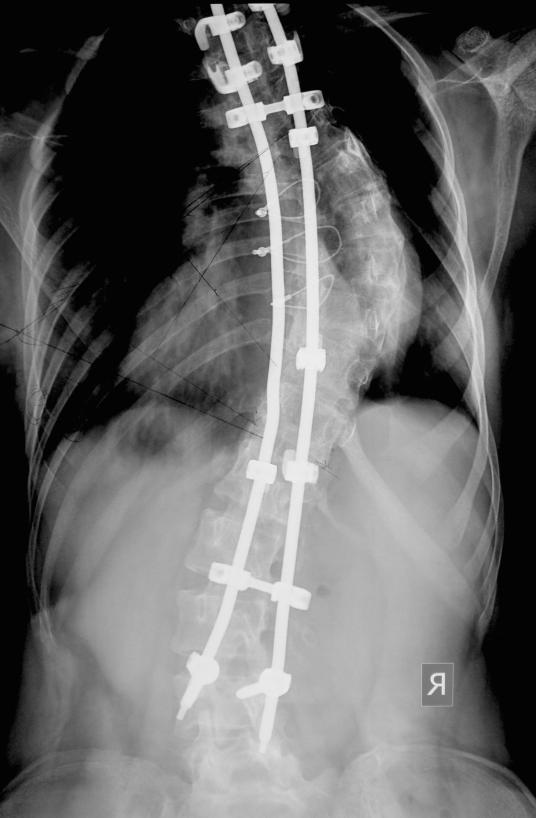

Post operative X-rays standing erect PA & Lateral, after 10 days of surgery. Clinical picture after a month. Segmental fixation with hooks, pedical screws & rods.

Adolescent Idiopathic Scoliosis

Thorascopic anterior release f/b usage of segmental instrumentation posteriorly & autograft for fusion

Usage of per-op spinal cord monitoring

Post op Xray